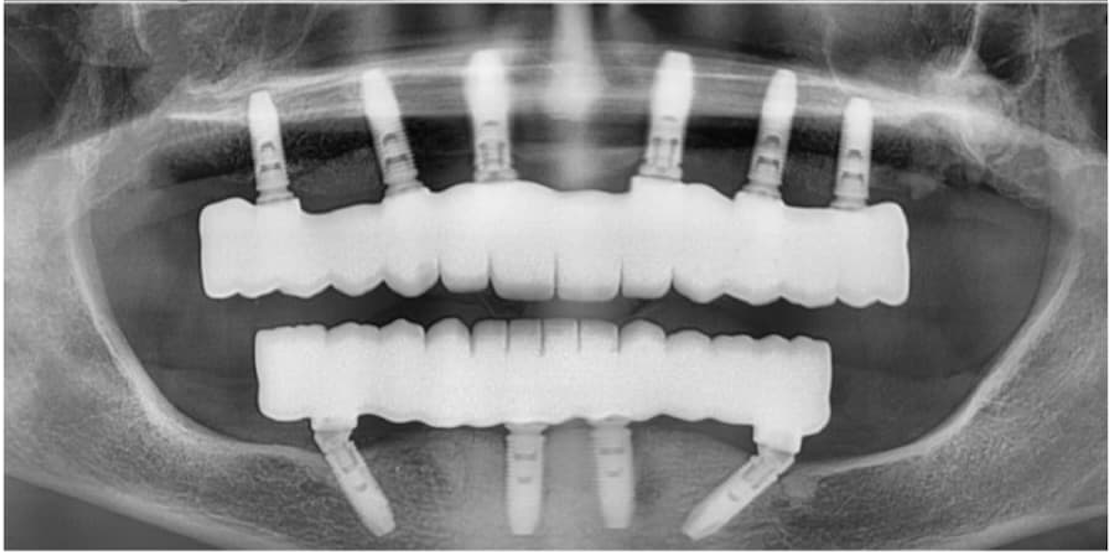

Zygomatic Implants Case Study

Case Study

Advanced Zygomatic

Implant Rehabilitation

Fixed prosthetic rehabilitation with zygomatic implants for a patient presenting with extreme bone deficiency and failed previous implant attempts from another facility.

In this complex case where traditional implant treatments were technically impossible to apply, the ZAGA Concept allowed us to provide a stable, long-term solution through specialized zygomatic surgery, restoring both function and aesthetics.

• Removal of failed implants from external centers

• Severe bone loss management via Zygomatic Concept

• Full functional and aesthetic fixed restoration